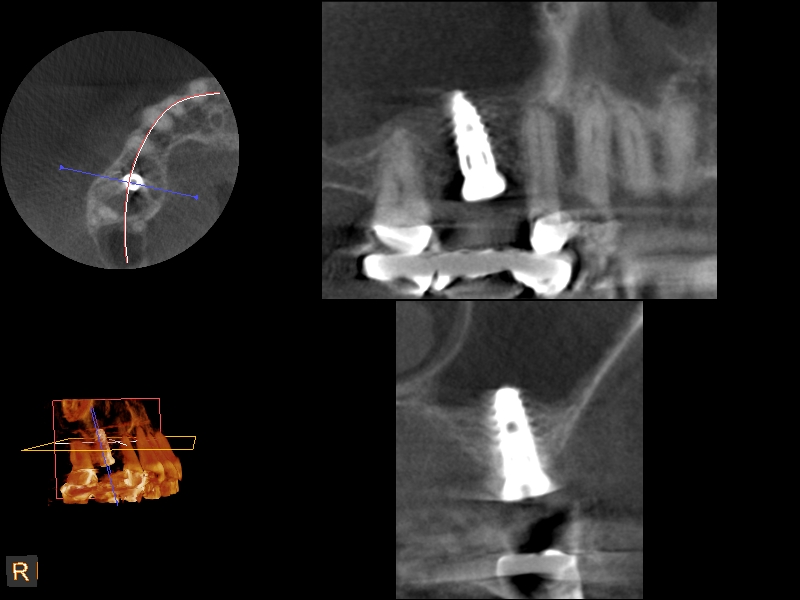

A 4-month CBCT scan (Kodak 9000D) of

implant No. 14.

Fig. 7

Because the bone grafting materials used in this technique need physical stability during healing to support the raised membrane, there is a high probability that significant shrinkage of the graft will occur as it heals and matures if only non-demineralized material is used. For these reasons, a composite graft using calcium sulfate, DFDBA, and mineralized particulate bone is used. A 50:50 mixture by volume of mineralized bone grafting material and DFDBA is used, to which approximately 40% calcium sulfate by volume is added. A higher percentage of calcium sulfate is used relative to that described for composite grafting in other uses, because some of the calcium sulfate will wash out during bone packing. Another advantage to this composite graft is that it is not as radiopaque as a purely mineralized graft. This allows radiographic monitoring of the bone healing around the implant, which can be used to time abutment placement on the implant. This is demonstrated in Figure 4 and Figure 5, which are radiographs taken on the day of the initial surgery showing the radiographic appearance of the composite graft, implant, and graft, and in Figure 6, a 5-month postoperative radiograph with the abutment in place. The old floor of the sinus is indistinguishable from the area of new bone. Figure 7 shows a CBCT scan (Carestream Dental, www.carestreamdental.com) taken at 4 months with the old floor of the sinus indistinguishable from the new bone formed.

CBCT scan (Kodak 9000D) showing 3.5-month postoperative of implant No. 3 in place. Note homogeneous appearance of the bone.

Fig. 12